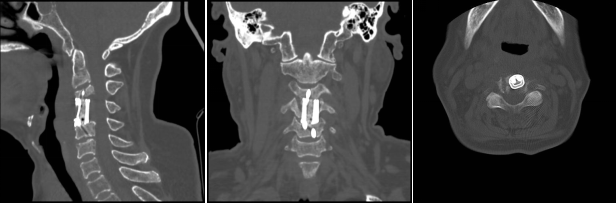

術(shù)后影像學(xué)顯示,植入內(nèi)植物位置滿意,與終板匹配性良好,穩(wěn)定性佳。術(shù)后患者生命體征平穩(wěn),癥狀明顯緩解,活動(dòng)良好,目前已出院。

經(jīng)過周密細(xì)致的術(shù)前討論,脊柱外科團(tuán)隊(duì)最終決定為該患者擬行頸椎病灶清除、椎管減壓+植骨融合術(shù),考慮患者高齡,又有骨質(zhì)疏松,為更好保障重建穩(wěn)定性,采用3D打印進(jìn)行術(shù)前規(guī)劃設(shè)計(jì)假體進(jìn)行植入,此款融合器是國內(nèi)首款SLM激光打印融合器,具有解剖匹配、骨融合確切等優(yōu)勢,為取得優(yōu)良手術(shù)效果打下了堅(jiān)實(shí)基礎(chǔ)。